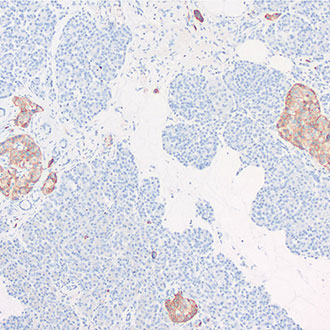

IHC

免疫组织化学(IHC)